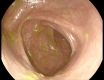

Introduction: Aseptic hepatic abscesses are a highly uncommon phenomenon and even more rare in the spectrum of extraintestinal manifestations of inflammatory bowel disease. Part of the spectrum of "neutrophilic disease," both the pathogenesis and the optimal management of these aseptic abscesses remain unclear. In the context of inflammatory bowel disease, sometimes these abscesses appear despite normal endoscopic findings.

Case presentation: We describe a highly uncommon case of aseptic hepatic abscess formation in a patient with inflammatory bowel disease.